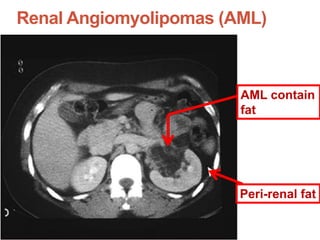

Renal Angiomyolipomas (AML)

Frequency in TSC patients: ~ 40 – 70 %

 Diagnosis : demonstration of FAT in

the Tumor

AML contain

fat

Peri-renal fat